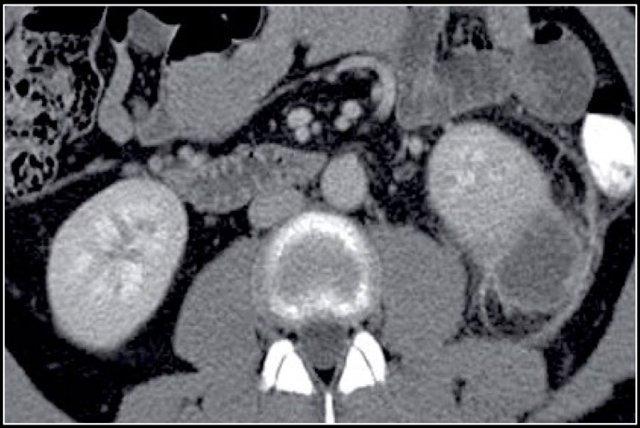

Trong trường hợp này, có các vùng giảm tỷ trọng ở cả hai thận.

Chỉ dựa trên hình ảnh, chẩn đoán phân biệt chính bao gồm viêm bể thận đa ổ, u lympho và di căn.

Bệnh nhân này có tiền sử nhiễm trùng đường tiết niệu, các đợt đau hông lưng và không có tiền sử u nguyên phát hay u lympho.

Do đó, chẩn đoán là viêm bể thận.

Chụp CT 4 tháng sau cho thấy sự ngấm thuốc bình thường của cả hai thận; các bất thường thận trên lần chụp đầu tiên do đó phù hợp với một đợt viêm bể thận đa ổ.